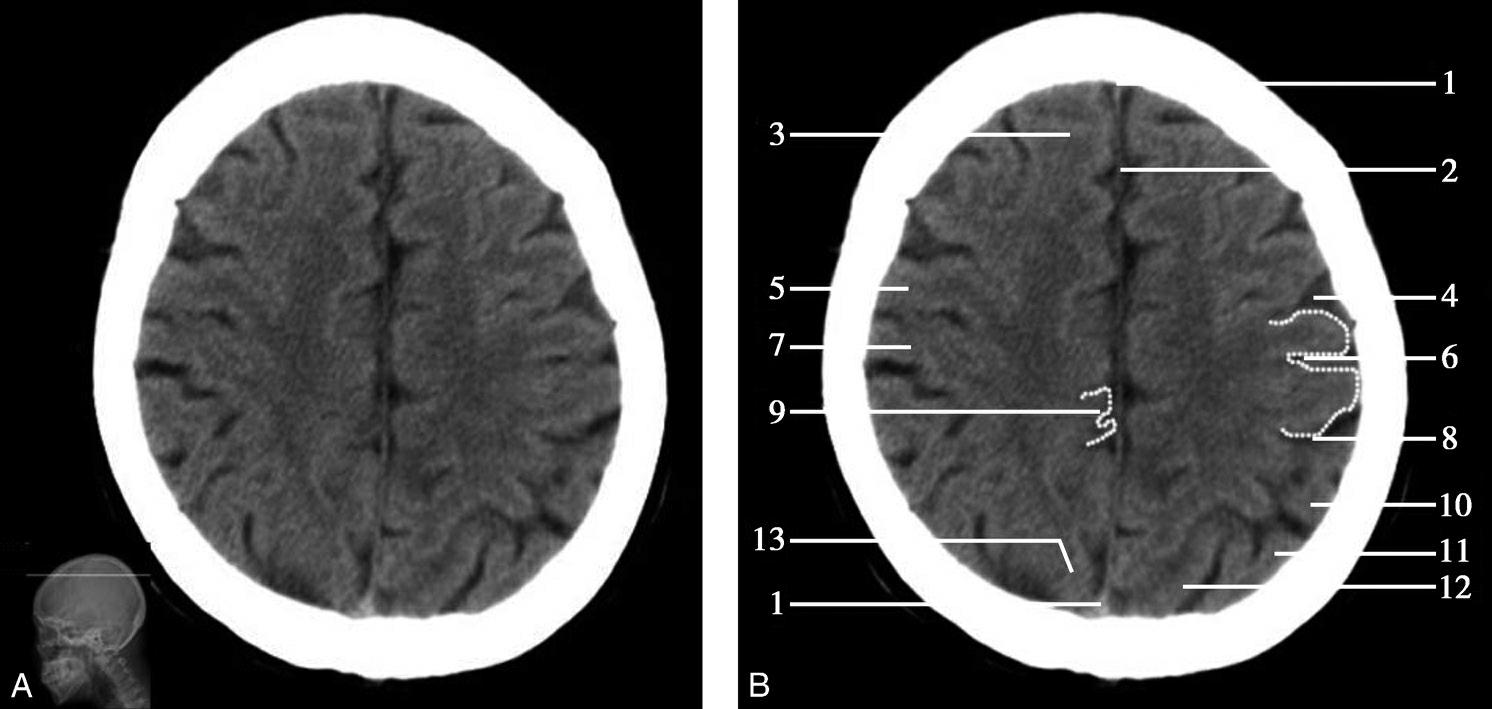

重要结构:尾状核体部、侧脑室体部、放射冠、额叶、顶叶(图1-2-34~图1-2-36)。

图1-2-34 尾状核体部层面

A.横断面;B.横断面标注

1.上矢状窦;2.大脑镰;3.额叶;4.颞肌;5.扣带回;6.胼胝体;7.透明隔;8.中央前沟;9.中央前回;10.中央沟;11.中央后回;12.中央后沟;13.尾状核体部;14.岛盖;15.放射冠;16.脉络膜丛;17.侧脑室体部;18.顶叶;19.顶枕沟;20.枕叶

双侧侧脑室体部呈凹缘向外侧的镰刀状居中线两旁,以透明隔为界。尾状核体部紧贴侧脑室体部外侧壁,其外侧为双侧大脑半球白质,即放射冠,再外侧为岛盖。大脑半球内侧面被胼胝体分成前后两部,前部由前向后为额内侧回和扣带回,后部由前向后为扣带回、楔叶和舌回。大脑半球外侧面的脑回由前向后依次为额上回、额中回、额下回、中央前回、中央后回、缘上回、角回。顶枕沟位于半球内侧面后部,沟较深,呈水平走向,易于辨认。中央沟作为额叶与顶叶的分界线在此层面有时不易识别。